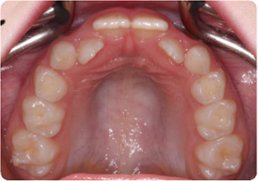

Each case shows the front view and an arch or side view, before and after BioLign Method-guided treatment.

Overlapping teeth resolved through arch form restoration